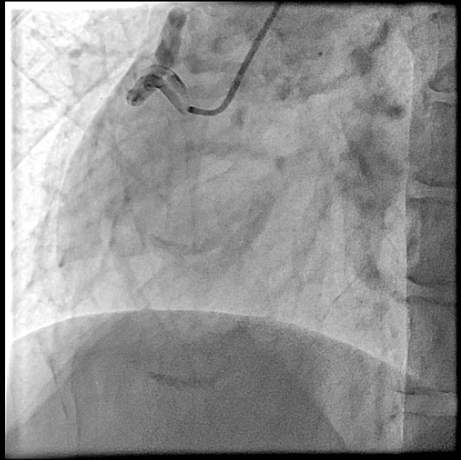

Right heart catheterization revealed a pulmonary capillary wedge pressure of 19 mmHg and mean pulmonary artery pressure of 47/27 mmHg. Pulmonary vascular resistance was 3.06 Wood units, with cardiac output of 4.9 L/min and Qp/Qs ratio of 1.24. Coronary angiography showed patent left main, LAD, and circumflex arteries. A small proximal LAD fistula and a large RCA fistula, both draining into the pulmonary artery, were identified.

The procedure was performed via left radial artery access. The right coronary fistula was engaged with a 6F AL1 guide catheter. A 5F microcatheter advanced an ASAHI Sion Black wire into the fistula tract. Given the fistula¡¯s large size and high flow, a two-device closure strategy was employed. A 7-mm AMPLATZER Vascular Plug 4 was initially deployed proximally, achieving partial flow reduction. To ensure complete occlusion, an 8-mm AMPLATZER Vascular Plug was subsequently positioned at the ostium. Final angiography confirmed marked flow reduction in the fistula while preserving native RCA flow. The small LAD fistula was left untreated due to minimal shunting. The procedure was completed without complications, and radial hemostasis was achieved.